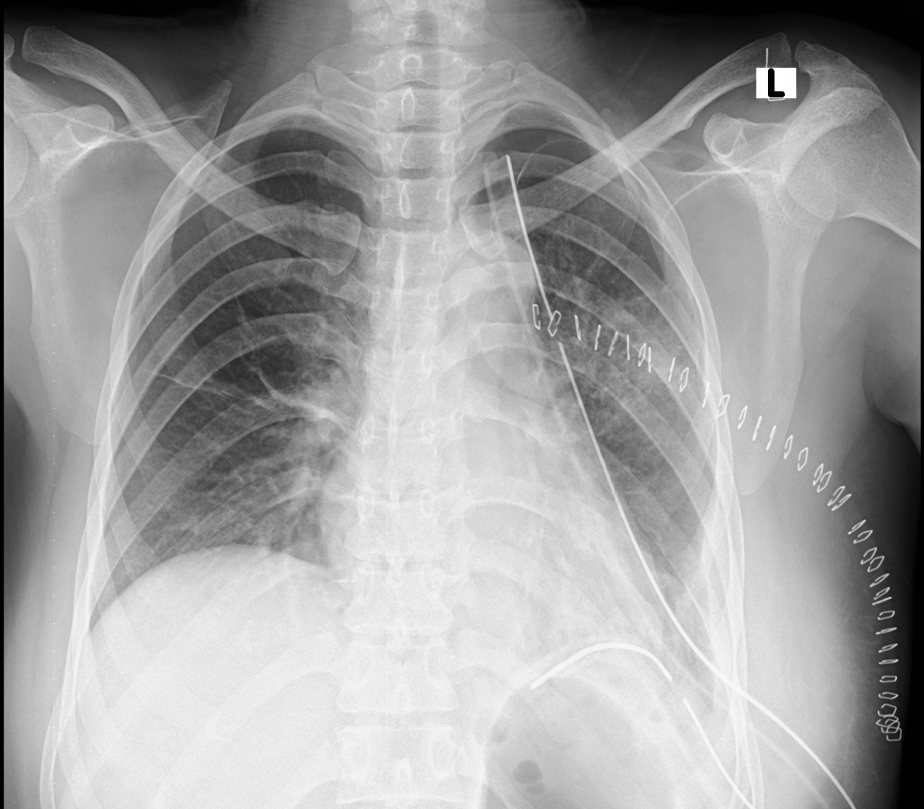

Figure 1. Chest x-ray at arrival showing an air-fluid level in the left hemithorax with contralateral mediastinal shift.

A 27-year-old woman presented to the emergency department with complaints of shortness of breath and cough with sputum for the last three days that had worsened since the morning of presentation. Her history was significant for gestational amenhorrea of 32 weeks. This was her second pregnancy. Her vital signs were within the normal limits. A physical exam revealed absent breath sounds on the left side and a gravid uterus of about 30 weeks. A chest x-ray was done which showed air fluid levels in the left chest with upward pointing meniscus. The authors’ differential included a diaphragmatic hernia, diaphragmatic eventration, hydatid cyst, and loculated empyema. An obstetrician was consulted, and after an examination, they declared that the patient was in labor. She delivered a healthy baby through normal vaginal delivery. After labor, she was comfortably lying in bed with normal vital signs and no active complaints. However, a little later, the patient started to become tachypneic and tachycardiac. Her respiratory rate was more than 50 per minute and heart rate was more than 140 per minute. An electrocardiogram was done which showed sinus tachycardia. She was shifted to the intensive care unit and was intubated for progressing respiratory failure. A nasogastric tube was passed and approximately more than two liters of gastric content was aspirated. An urgent echocardiogram was obtained which showed a right ventricle strain and a dilated Inferior vena cava without respiratory variation. The patient was urgently shifted for a computed tomography of the chest with intravenous contrast, which revealed a large diaphragmatic hernia on the left side. The stomach, omentum, splenic flexure of the colon, the descending colon, small bowel, spleen, and tail of the pancreas were all present in the left chest cavity. There was a mediastinal shift to the right, and the left lung was collapsed. The right lower lobe also showed signs of compression atelectasis.